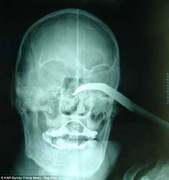

Chuyện hy hữu khi một người đàn ông bị móc sắt dài gần 5cm lún sâu vào hốc mắt một đoạn 5cm nhưng thị lực vẫn không hề hấn gì.

Kết quả CT Scan: ngoại vật hốc mắt trên có cản quang cho thấy đầu mũi kéo chưa xâm hại thành nhãn cầu và sọ não.